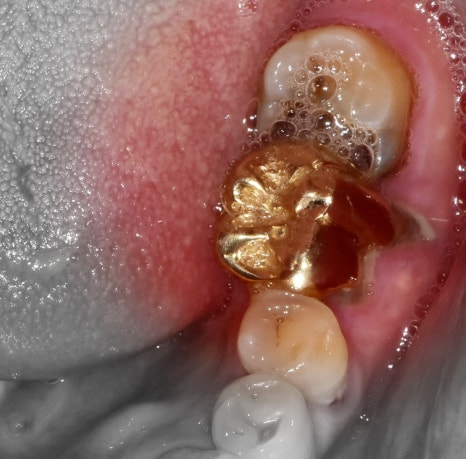

안녕하세요. 박현준 원장입니다. 아마.. 입 속에 크라운이 없으신 분들은 거의 없으실 겁니다. 다들 하나쯤은 가지고 있으시죠? 근데, 그 보철물을